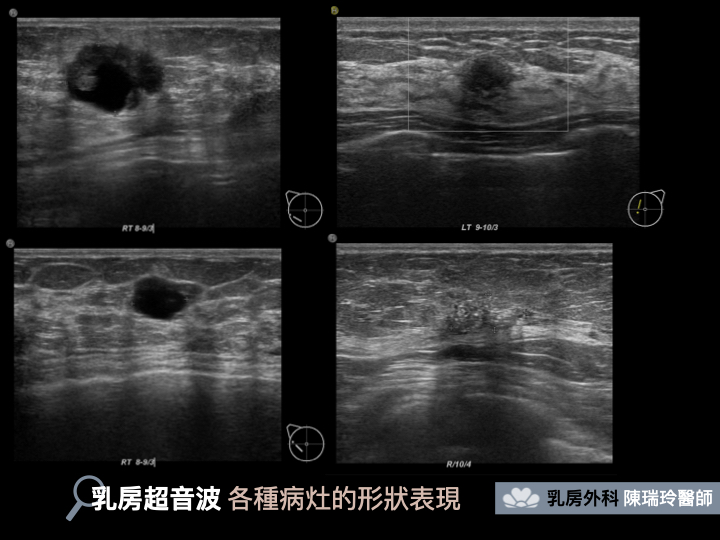

乳房超音波是利用手持探頭在皮膚上滑動,利用聲納的原理接收反彈回音成像;在操作過程中,醫師或專業的技術員可以利用各種不同的角度移動探頭,對於腫瘤、腺瘤、囊腫等病灶,可以得到很具體的形狀、大小、立體概念、相對位置等資訊。一般女性對於超音波想必不陌生,像是懷孕時婦產科醫師會利用超音波檢查寶寶的身體狀況,正是利用超音波在立體構造的強項,連幾隻手指頭、有沒有小雞雞都看得出來!而且音波不是放射線,沒有接觸劑量累積可能造成的疑慮,更不會有擠壓乳房造成的疼痛問題,是一個非常方便且直接的檢查方式。

在生育年齡階段有許多乳房問題困擾的族群中,常見的乳房良性腫瘤、乳腺炎、乳房疼痛,超音波都是很方便的鑑別診斷工具。另外對於乳腺組織較為緻密的亞洲女性來說,確實也有一小部分的乳癌是沒辦法在乳房攝影下被看到的;所以我們也會建議30歲以上女性接受一年一次乳房超音波檢查,可以讓檢查和保護更加滴水不漏。

簡單來說,乳房攝影和乳房超音波在原理上完全不同,適合的族群、病灶也完全不同,所以是無法互相被取代的兩種檢查。像是很常見的乳房良性腫瘤,可以藉由乳房超音波觀察它的大小、形狀來做確認,但是乳房攝影的平面影像卻無法幫忙我們做出判斷;如同鹽巴麵粉那樣細小的乳房鈣化,這些偶爾可能有早期乳癌病變的病灶,可以從乳房攝影的高清影像做鑑別,但卻無法在乳房超音波底下被看到。